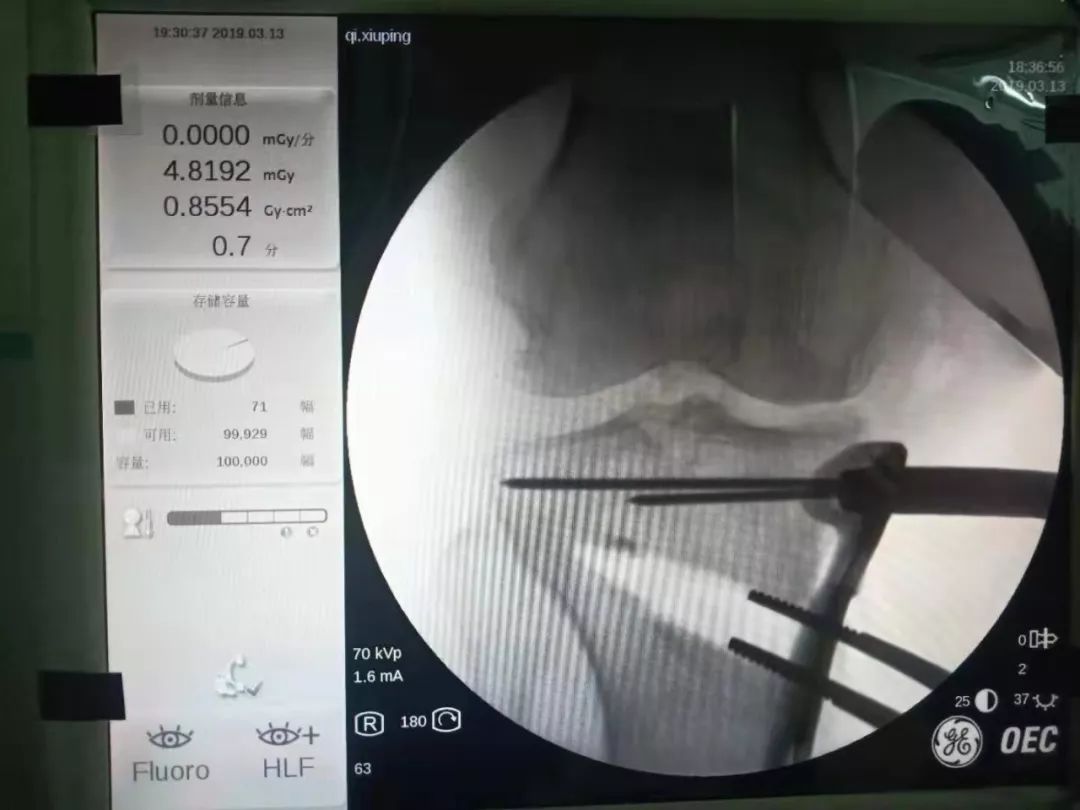

术前与兰大二院关节外科吴萌教授积极准备,制定了详尽的治疗方案及手术策略,决定进行腰硬联合麻醉下“左侧胫骨高位截骨术”。2019年3月13日,在麻醉科副主任郭海燕的配合下,我院骨与软组织科主任张华文带领手术团队,在吴萌教授的帮助指导下顺利完成了手术。手术历时约2小时,按术前计划圆满完成了手术,纠正了患者左下肢力线,降低了膝关节内侧间室压力。目前患者恢复良好。